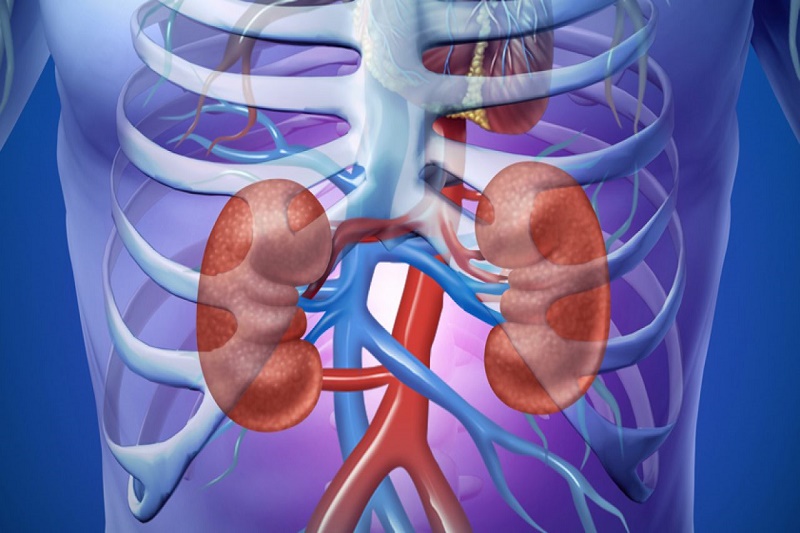

Nếu không kiểm soát tốt đường huyết, bệnh có thể gây ra hàng loạt biến chứng nguy hiểm như tổn thương tim mạch, đột quỵ, đặc biệt là tổn thương vi mạch tại thận, dẫn đến suy thận mạn, thậm chí phải chạy thận hoặc ghép thận.

Ảnh minh họa.